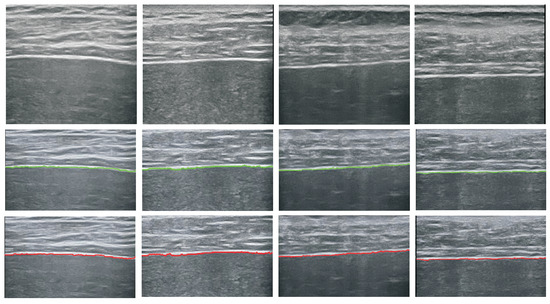

5.1. Performance of the Detector

5.2. Performance of Image Classification

5.2.1. Impact of Detection Error